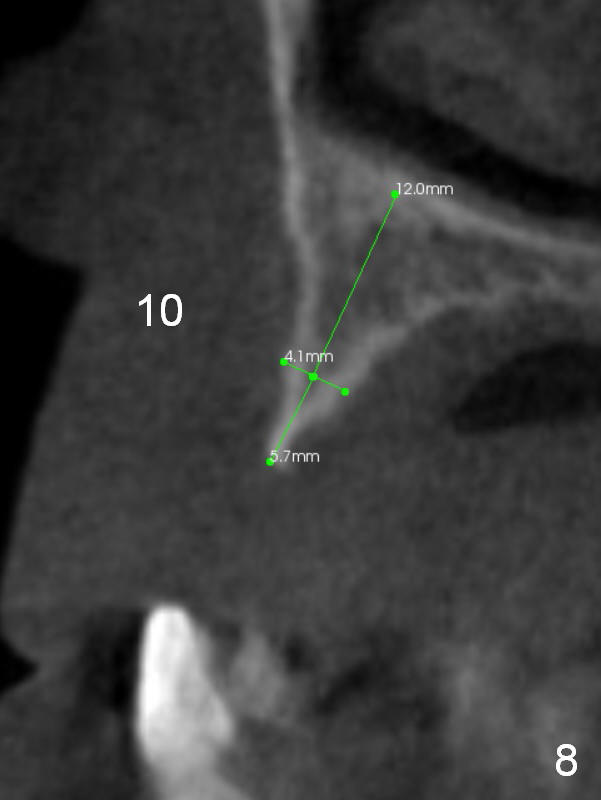

After implant reconstruction of the lower right and left (including #19) regions, the same treatment is considered in the atrophic anterior maxilla (#8-13) for anchorage for upper left molar cross bite correction. The smallest implants are to be placed in the each of the sites with different strategies. For example, at the site of #8 (Fig,1,2), ridge split with wheel (Fig.3) and microsteotomes (Fig.4) are used to place 1-piece implant (3x14 mm). The site of #9 has a pointed ridge and a wide base (Fig.6); a 1-piece angled implant (3x14 mm 15 °) is placed palatally (Fig.7). The ridge and base at #10 are narrow (Fig.8); after truncating the pointed ridge, a 2.0 or 2.5 mm 1-piece implant is placed parallel to the palatal wall (Fig.9).